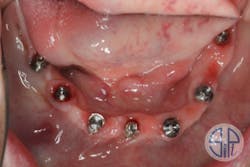

A full-arch restoration on transmucosal abutments was planned. A rigid resin pattern, open-tray, implant level impression was taken (figure 1). The laboratory provided the dentist with straight, transmucosal abutments (figure 2) and a verification jig that was used to verify occlusion, phonetics, and esthetics (figure 3).